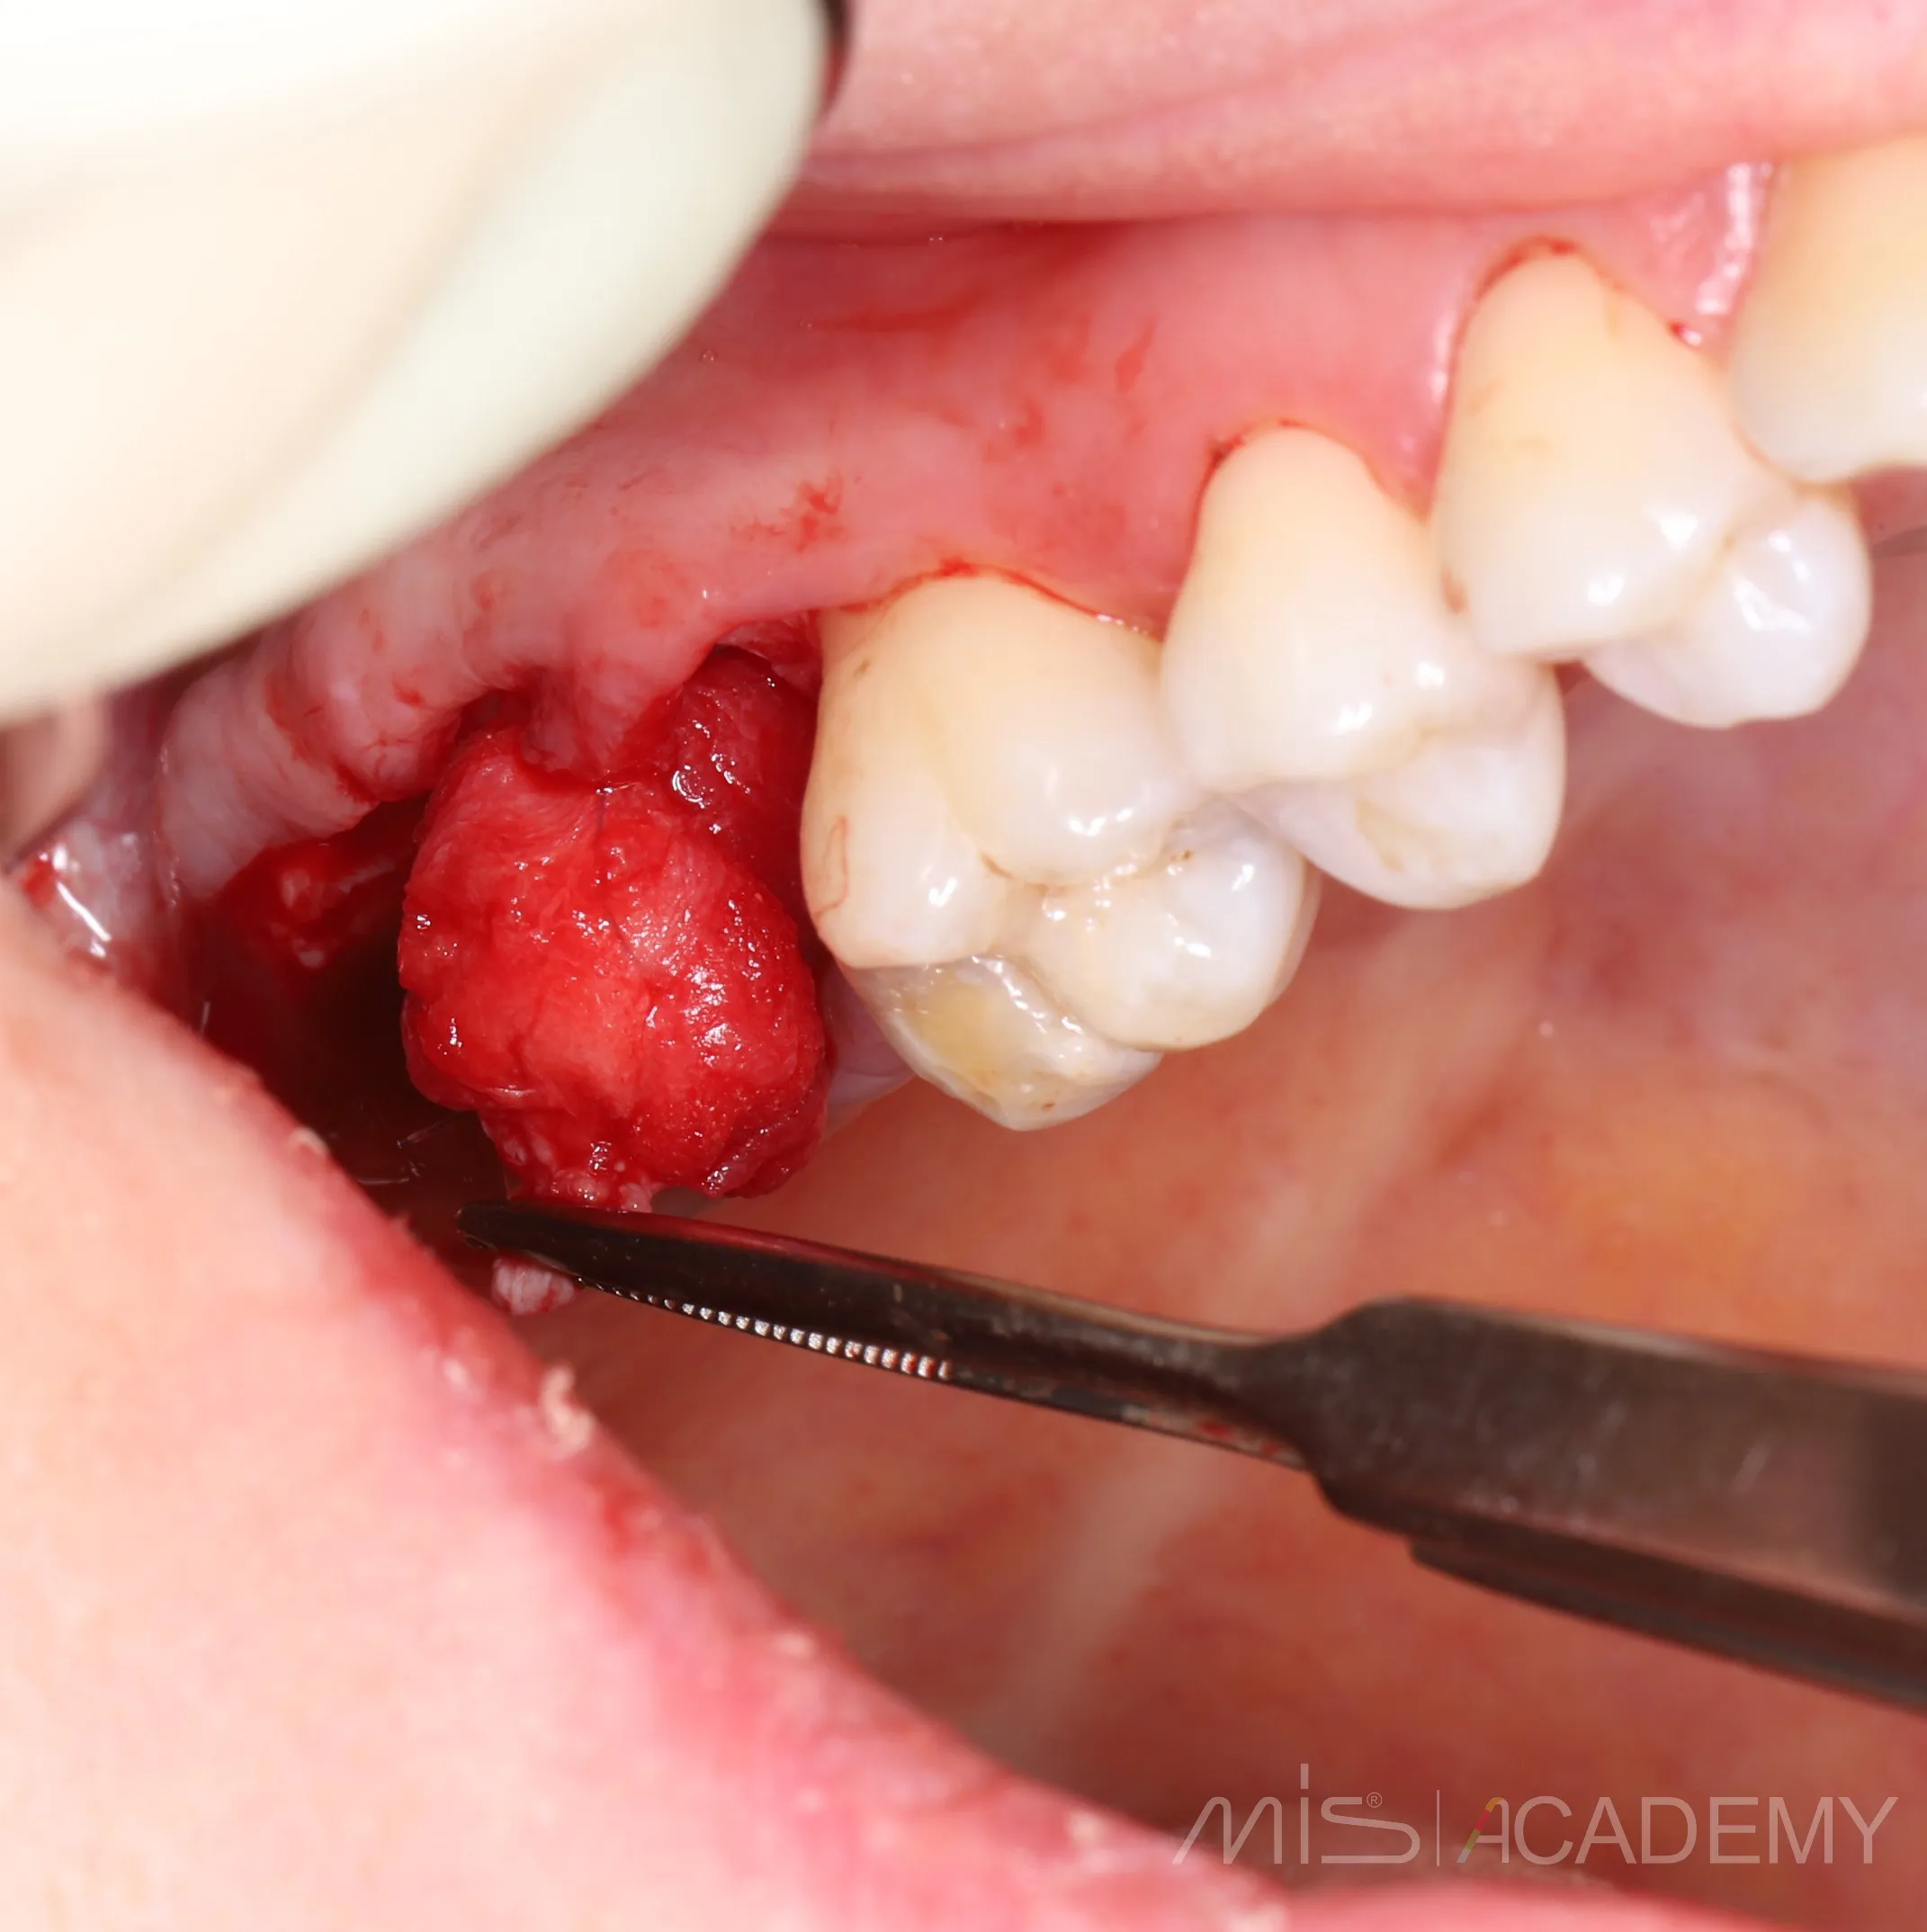

2 года назад закрыл соустье с пазухой в обл 17 зуба лоскутом с бугра «через себя»

Да, я подсмотрел это способ у Артура Политова. Сейчас пациентка пришла на плановый осмотр с другой проблемой,